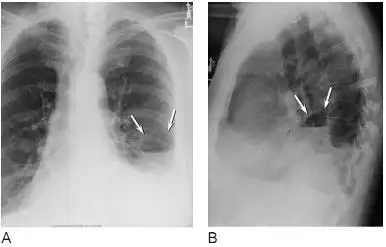

5种肺部感染的影像学鉴别多图